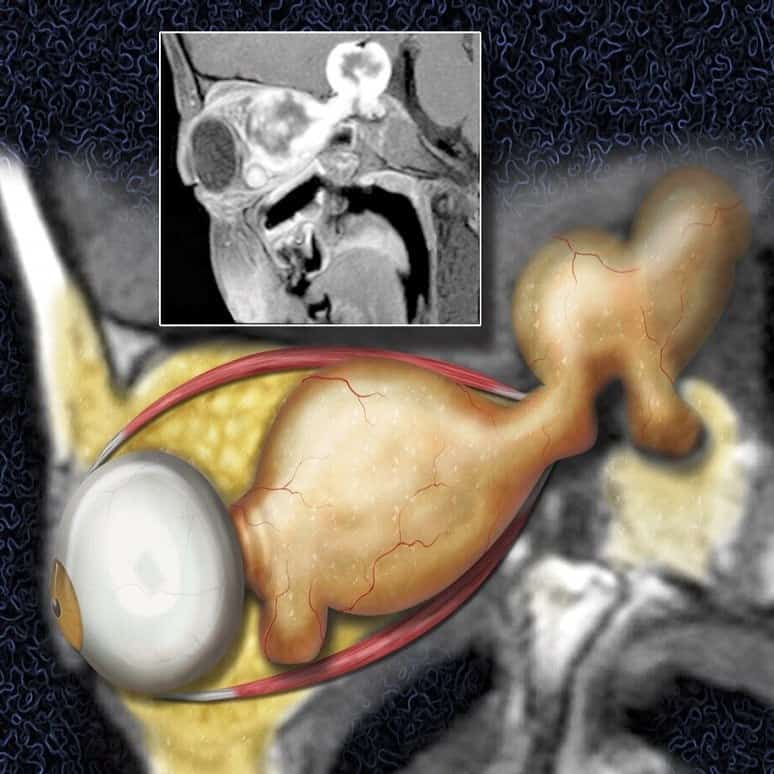

* Nhổ rễ thần kinh

– Có thể nhổ hoàn toàn rễ trước và rễ hoặc nhổ rễ trước ra khỏi cột tuỷ.* Giả thoát vị màng tủy

kinh.

– Hình ảnh 1 ổ dịch, tăng tín hiệu mạnh trên T2W và giảm tín hiệu trên T1W, tạo nên hình ảnh mất cân xứng so với bên đối diện.* Đụng dập